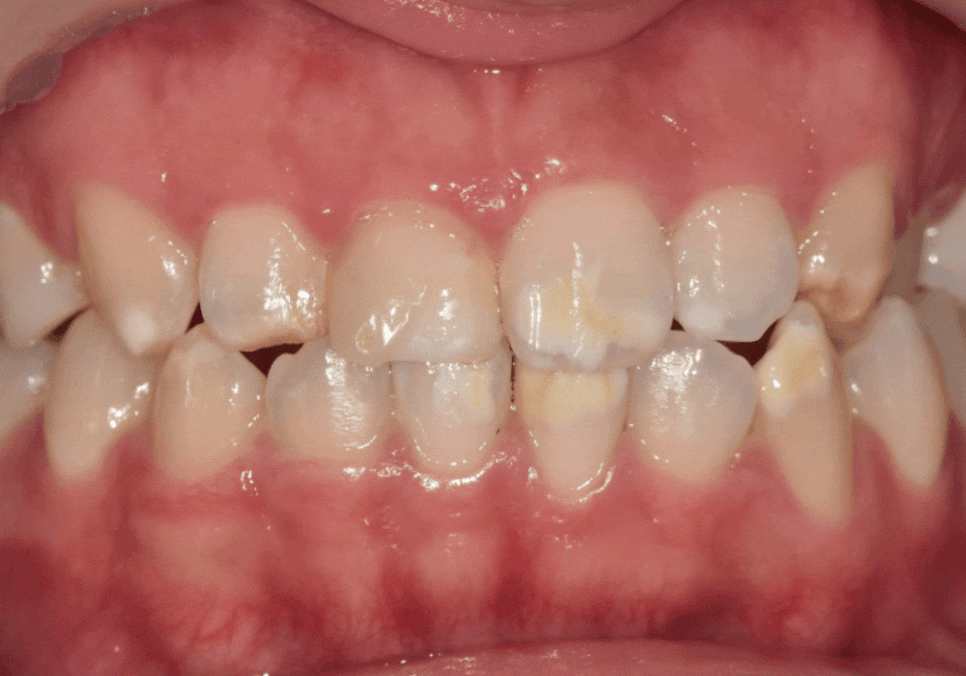

바로 교합,

즉 치아 맞물림 상태였는데요,

확인 결과,

양쪽 송곳니 부위가

긴밀하게 맞물리고 있었고,

씹을 때 힘이 직접적으로

전달되는 구조였습니다.

이러한 상태에서는

얇은 라미네이트가

장기적으로 부담을 받을 가능성이 있습니다.

그래서

힘을 상대적으로 덜 받는

앞니는 라미네이트,

씹는 힘이 집중되는

송곳니 부위는

강도가 쎈 지르코니아 크라운으로

치료 방법을 나누어 선택했습니다.